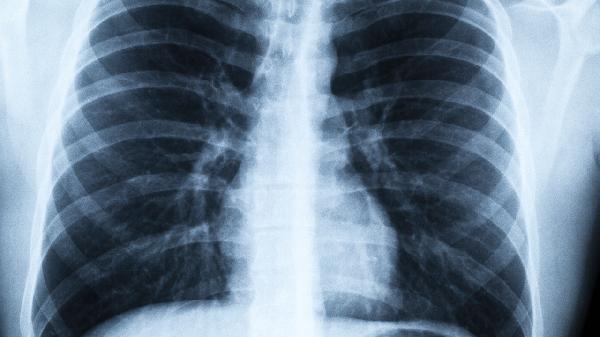

3.呼吸频率改变。安静状态下每分钟呼吸超过20次,或稍微活动就气喘,提示肺部换气功能下降。

别等发烧才警惕,当出现不明原因乏力、久咳不愈时,建议尽快做血常规和肺部听诊。特殊时期,床头可以备个血氧仪,指尖血氧饱和度低于95%就要引起重视。健康的人体就像精密的生态系统,有时候最危险的往往不是熊熊烈火,而是那些闷烧的暗火。